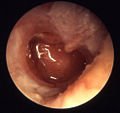

Chronic suppurative otitis media involves a perforation (hole) in the eardrum and active bacterial infection within the middle ear space for several weeks or more. There may be enough pus that it drains to the outside of the ear (otorrhea), or the purulence may be minimal enough to only be seen on examination using a binocular microscope. This disease is much more common in persons with poor Eustachian tube function. Hearing impairment often accompanies this disease.

Instead of the infection and eardrum perforation resolving, however, drainage from the middle ear can become a chronic condition. As long as there is active middle ear infection, the eardrum will not heal. The World Health Organization defines Chronic Suppurative Otitis Media (CSOM) as “a stage of ear disease in which there is chronic infection of the middle ear cleft, a non-intact tympanic membrane (i.e. perforated eardrum) and discharge (otorrhoea), for at least the preceding two weeks” (WHO 1998). (Notice WHO’s use of the term serous to denote a bacterial process, whereas the same term is generally used by ear physicians in the United States to denote simple fluid collection within the middle ear behind an intact eardrum. Chronic otitis media is the term used by most ear physicians worldwide to describe a chronically infected middle ear with eardrum perforation.)